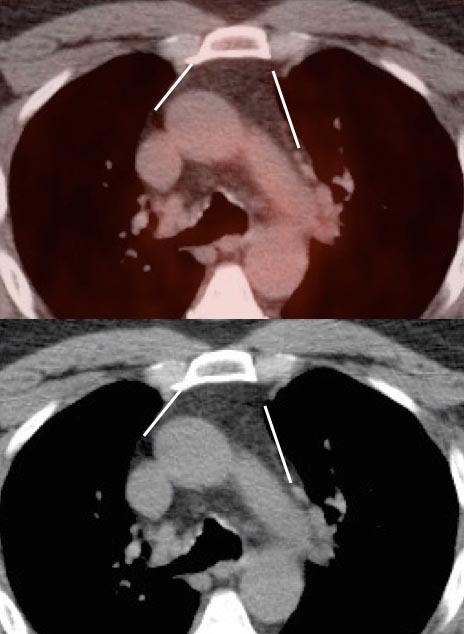

Morphology of the Thymus:

- Before considering any thymic uptake “normal”, it important that the thymus have a relatively normal CT appearance — somewhat triangular on the axial and coronal views, with straight or concave borders.

- When prominent residual thymic tissue is present, it typically demonstrates a “fluffy” appearance (a rather unprofessional descriptor, but quite illustrative).

- If the thymus is irregularly enlarged, has nodular component or is expanding the mediastinal borders (which may appear convex), the possibility of malignancy should be considered.